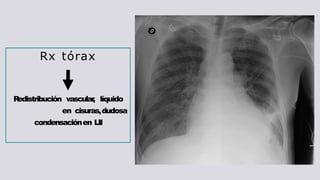

Rx tórax

R

edistribución vascular

, líquido

en cisuras,dudosa

condensaciónen LII

Rx tórax R edistribución vascular ,líquido en cisuras,dudosa condensaciónen LII